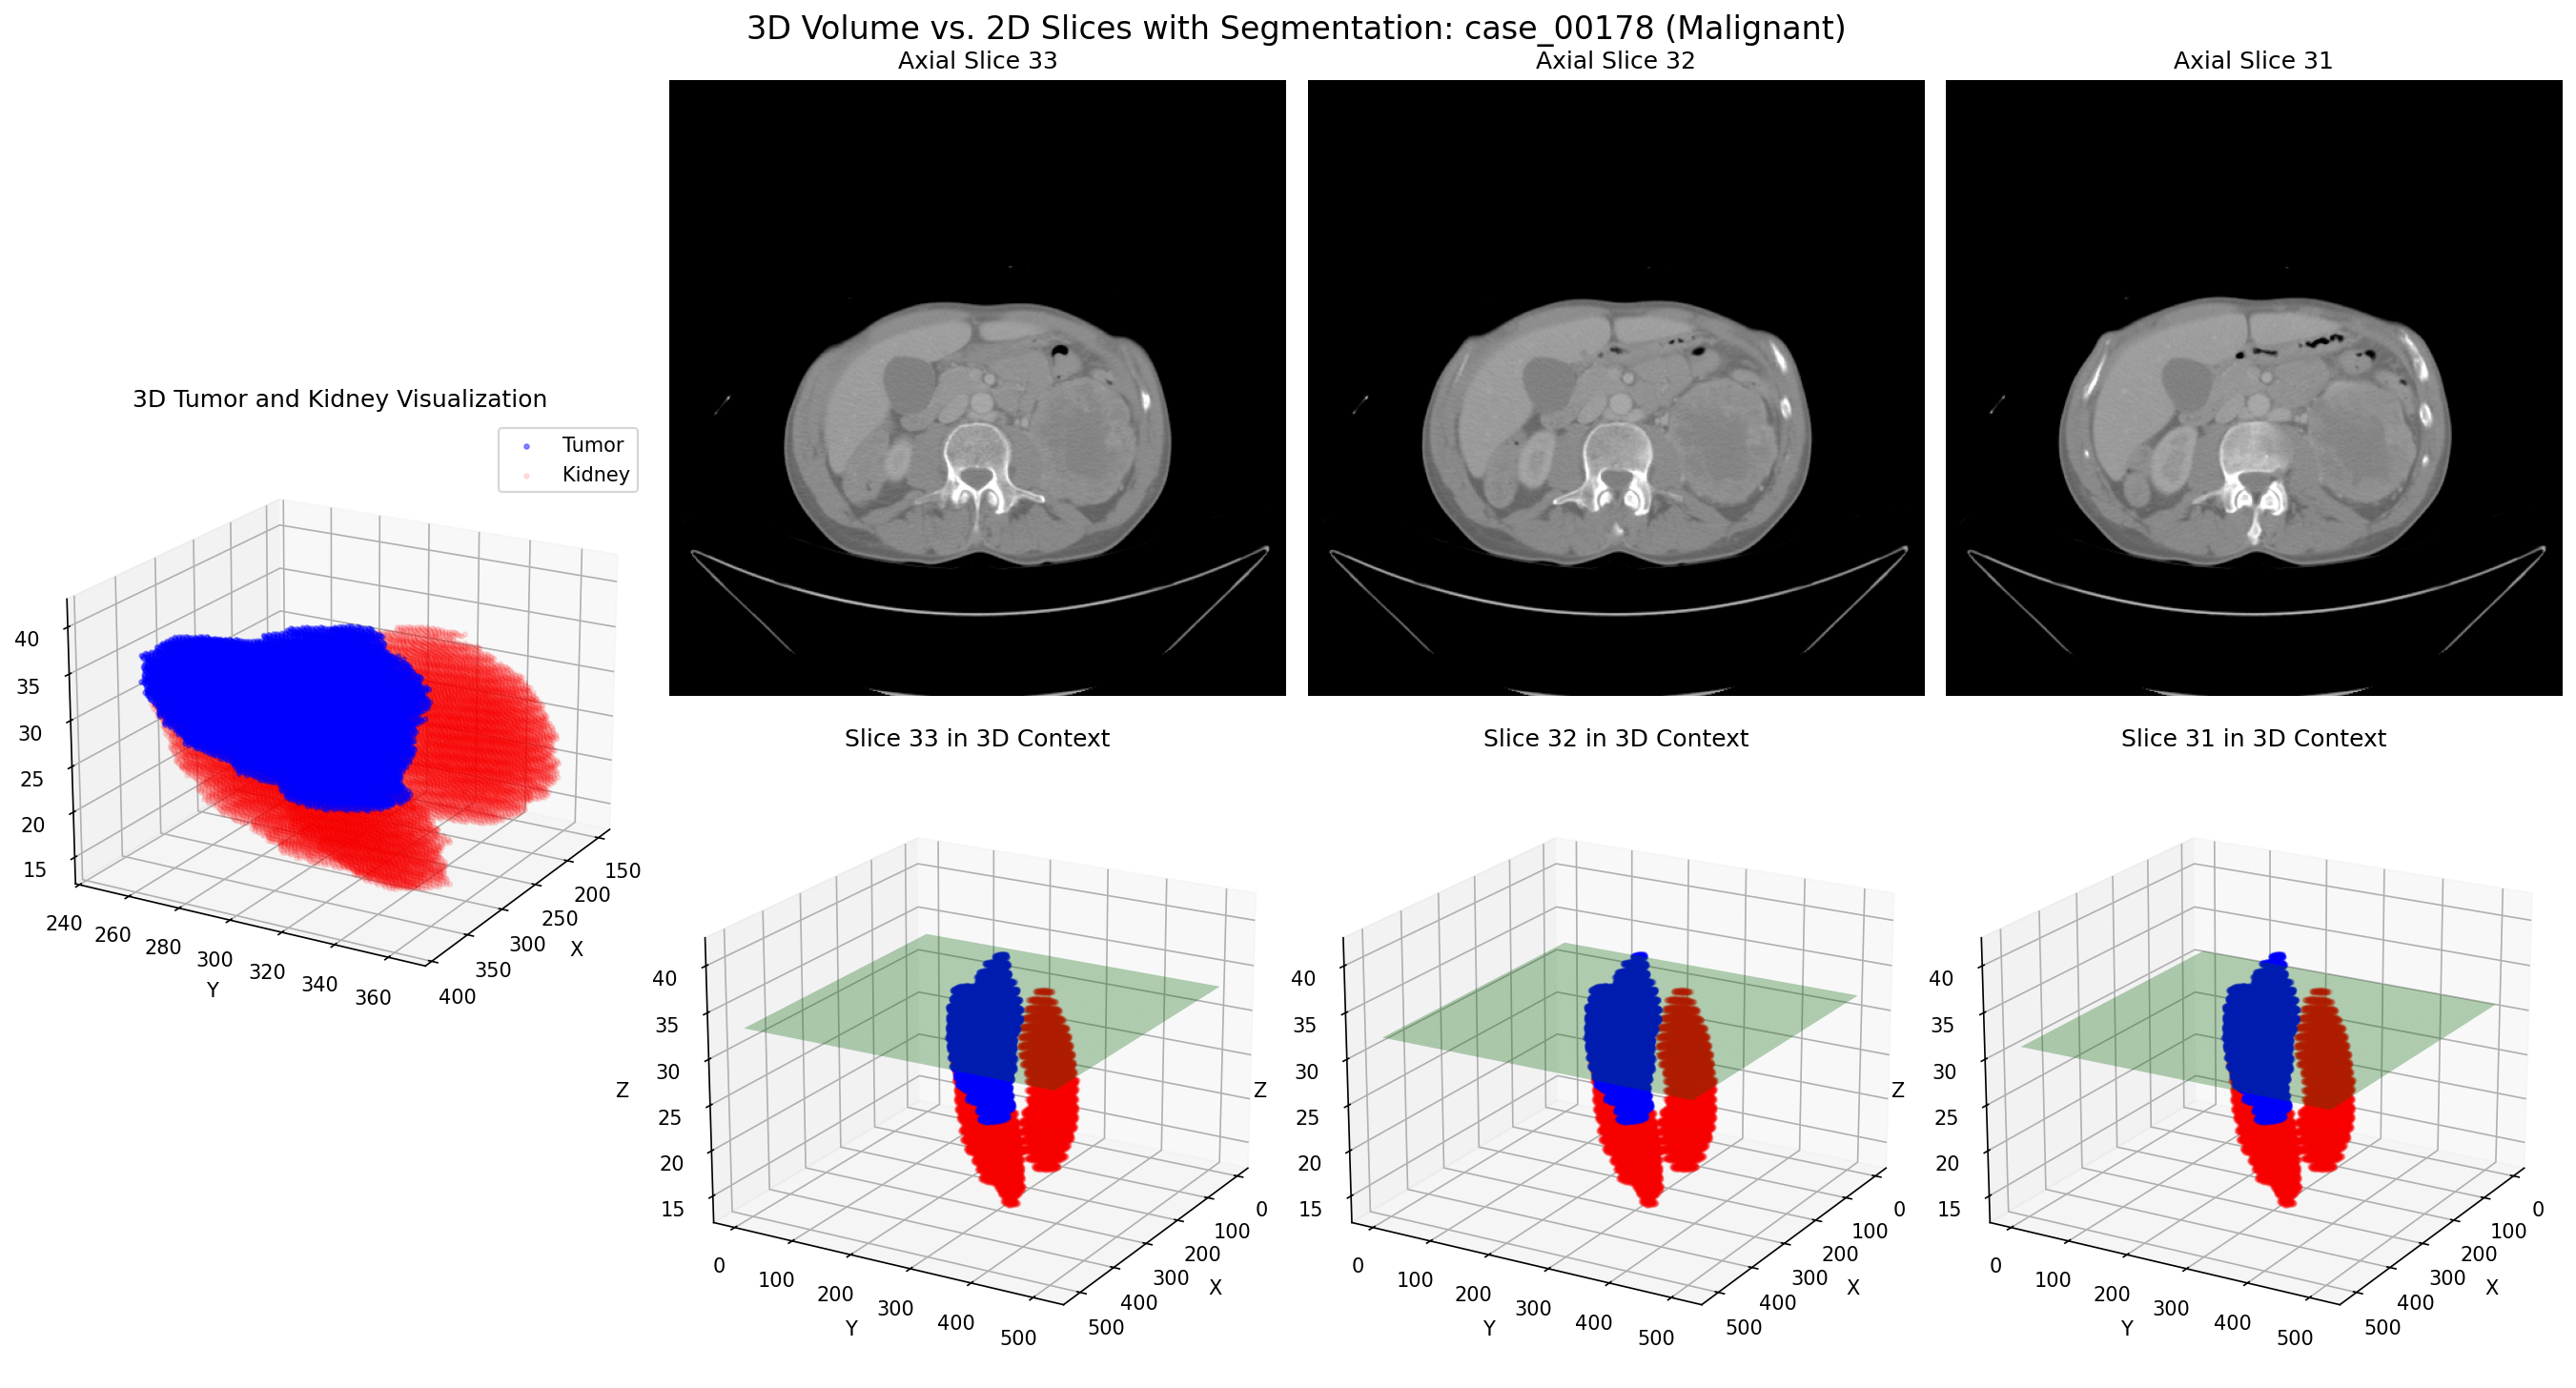

3D rotation of benign kidney tumor - Case 00178

This animation shows the 3D representation of a benign kidney tumor, which typically has more well-defined boundaries, smoother surfaces, and more homogeneous internal structure compared to malignant tumors. These 3D characteristics need to be effectively captured in 2D slices for model training.

Case 00178: 3D volume (top row) and corresponding 2D slices (bottom row) of a benign kidney tumor

Case 00178: Benign Tumor

These side-by-side comparisons show the relationship between 3D tumor volumes (top row) and their corresponding 2D slices (bottom row) for both malignant and benign cases. Our algorithm intelligently selects the most informative 2D slices from each 3D volume, capturing the key diagnostic features while generating multiple training examples from a single case.

Key insight: By converting each 3D case into multiple 2D slices, we effectively increased our training data by a factor of 8-10, with each slice carrying distinct morphological information about the tumor.